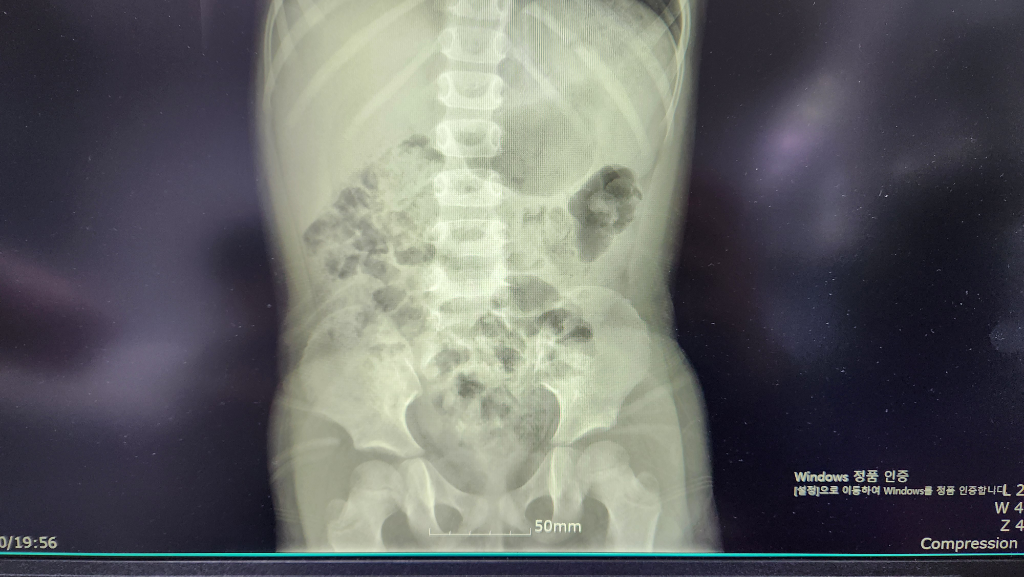

얼마 전 아이 감기때문에 엑스레이를 찍게(첫번째 사진)되었는데, 소아과 선생님께서 폐 부분을 먼저 설명해주시고~

아 그런데 이게 뭘까요~ 비장같은데, 하시면서 의아(?)해 하시면서 당장 문제되는건 아닌데 다음 엑스레이를 찍게될 기회가 있으면 계속 지켜보자고(?) 하셨습니다. 우연히 이렇게 찍힌게 아니라면 초음파 같은 추가검사가 필요 할 수도 있다고도 하시고요.촉진도 해보시고는 만져지지는 않아서 비장비대는 아닌데....아이들은 크게 보일 수도 있다 하면서 말끝을 흐리셨어요.

다녀와서 검색해보니 비장비대의 이유들은 무서운 이야기 뿐이더라구요, 걱정되는 마음에 응급실갔을 때(두번째 사진 23년5월, 세번째 사진 23년 11월) 엑스레이 사진을 받아왔는데 저기에도 실루엣은 보인다고 하셨습니다.

최근 24년 2월

• 1번 째 사진

• 엑스레이 검사에서는 비장을 자세하게 관찰할 수 없습니다. 올리신 엑스레이 사진을 통해서 구체적으로 비장에 문제가 있는지 판단할 수는 없으며 정밀 검사를 하겠다면 초음파나 CT 등 검사가 필요하겠습니다. 다만, 아이에게 관련 증상이 없고 혈액 검사에서도 이상이 없는 상황에서 정밀 검사가 꼭 필요한지는 애매하며 경과를 지켜보는 것도 가능하겠습니다.